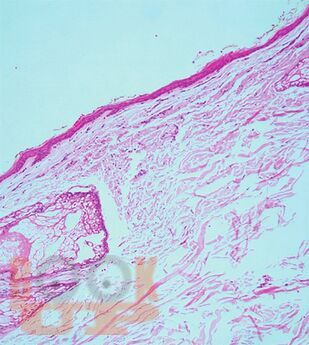

Судебно-медицинская экспертиза механической асфиксии и постасфиктической болезни

Судебно-медицинская экспертиза механической асфиксии и постасфиктической болезни : учебно-методическое пособие / М. А. Кислов, А. В. Максимов, О. В. Лысенко, Д. А. Карпов. - М. : Практическая медицина, 2025. - 140 c.. - (Библиотека судебно-медицинского эксперта). - ISBN 9785988118329. - Текст : электронный // ЭБС "Букап" : [сайт]. - URL : https://www.books-up.ru/ru/book/sudebno-medicinskaya-ekspertiza-mehanicheskoj-asfiksii-i-postasfikticheskoj-bolezni-19593927/ (дата обращения: 11.05.2026). - Режим доступа : по подписке.